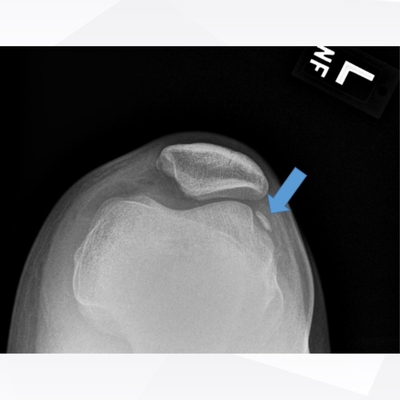

Click on an image below to view more info.